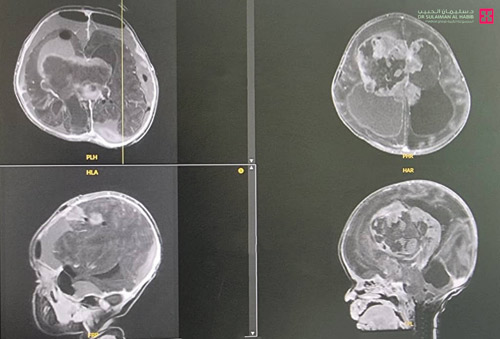

وأضاف د. مسعود أن الطفلة أسعفت إلى المستشفى وهي بحالة صحية معقدة، وتعاني من مشاكل في التنفس والبلع، بالإضافة إلى اضطراب وتسارع نبضات القلب، لذا تم إدخالها العناية المركزة مباشرة بسبب حالتها الصحية العامة، ومن ثم أجريت لها فحوصات دقيقة أظهرت وجود ورم ضخم في الغرفة الثالثة من الدماغ يضغط على مركز التنفس ومركز القلب.

وتابع د. مسعود قائلاً إن الفريق الطبي ناقش الحالة مع استشاري طب الأطفال، واستقر الرأي على التدخل الجراحي حيث أجرى الفريق عملية عاجلة للطفلة استغرقت 5 ساعات تم فيها استئصال الورم بدقة متناهية، مع المحافظة على الدم وتقليل النزف إلى الحد الأدنى، وتم استخدام مجموعة من التقنيات الحديثة كالميكروسكوب الحديث، ومراقبة الأعصاب والسونار. وقد تكللت العملية بالنجاح ونقلت الطفلة إلى العناية المركزة لحديثي الولادة، وتم وضعها على جهاز التنفس الاصطناعي لمدة «3» أيام، ثم تم فصل أجهزة التنفس الصناعي عنها ونقلها إلى غرفة التنويم، حيث بقيت 7 أيام تحسنت خلالها حالتها الصحية، وغادرت بعدها المستشفى. وقد أظهرت فحوصات ما بعد العملية، استئصال كامل الورم مع المحافظة على الأعضاء الحساسة المجاورة له من أعصاب ومراكز تحكم، إضافة إلى أن الفريق الطبي نجح في المحافظة على مستوى الدم رغم استمرار العملية 5 ساعات بالعمل المستمر على تقليل النزيف، حيث إن كمية الدم بالنسبة للأطفال بعمر أسبوعين لا تزيد عن «150» ملم وفقدان الكثير منه يعني وضع حياتهم على المحك.